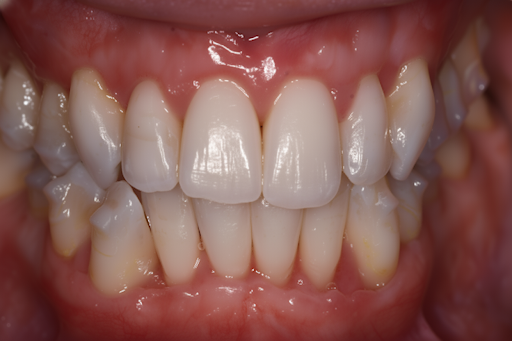

See What’s Possible

Explore the real transformations of patients who trusted us with their smiles.

Whether you’re looking for subtle tweaks or a full transformation, our cosmetic services are designed to help you feel confident at every step. We’ll discuss your goals, explore options, and help you decide what best suits your face, timeline, and budget.